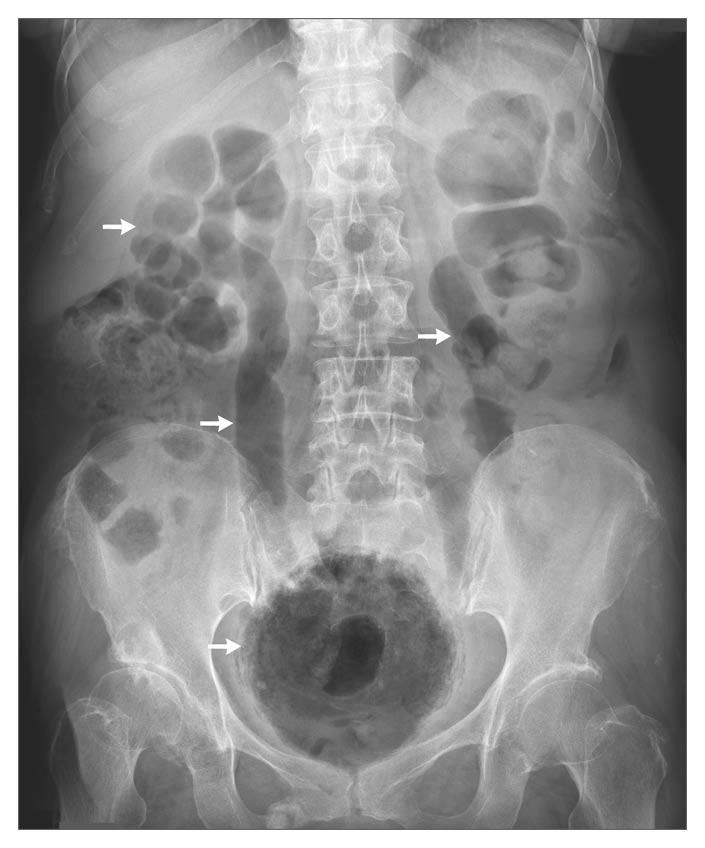

Plain abdominal radiography showed air throughout the urinary tract in the kidneys, ureters, and bladder (arrows).

The laboratory data showed elevated levels of blood glucose (519 mg per deciliter [28.8 mmol per liter]), C-reactive protein (37.1 mg per liter), and serum creatinine (1.6 mg per deciliter [141 μmol per liter]). The white-cell count was 11.9×10^3 per cubic millimeter.

Computed tomography confirmed the radiographic finding of acute emphysematous cystitis. A urine culture grew Escherichia coli, and the patient had a good response to antibiotic treatment.

Patients with diabetes mellitus have a predisposition to complicated urinary tract infections such as emphysematous cystitis, which is thought to be caused by fermentation of glucose by bacterial and fungal pathogens.